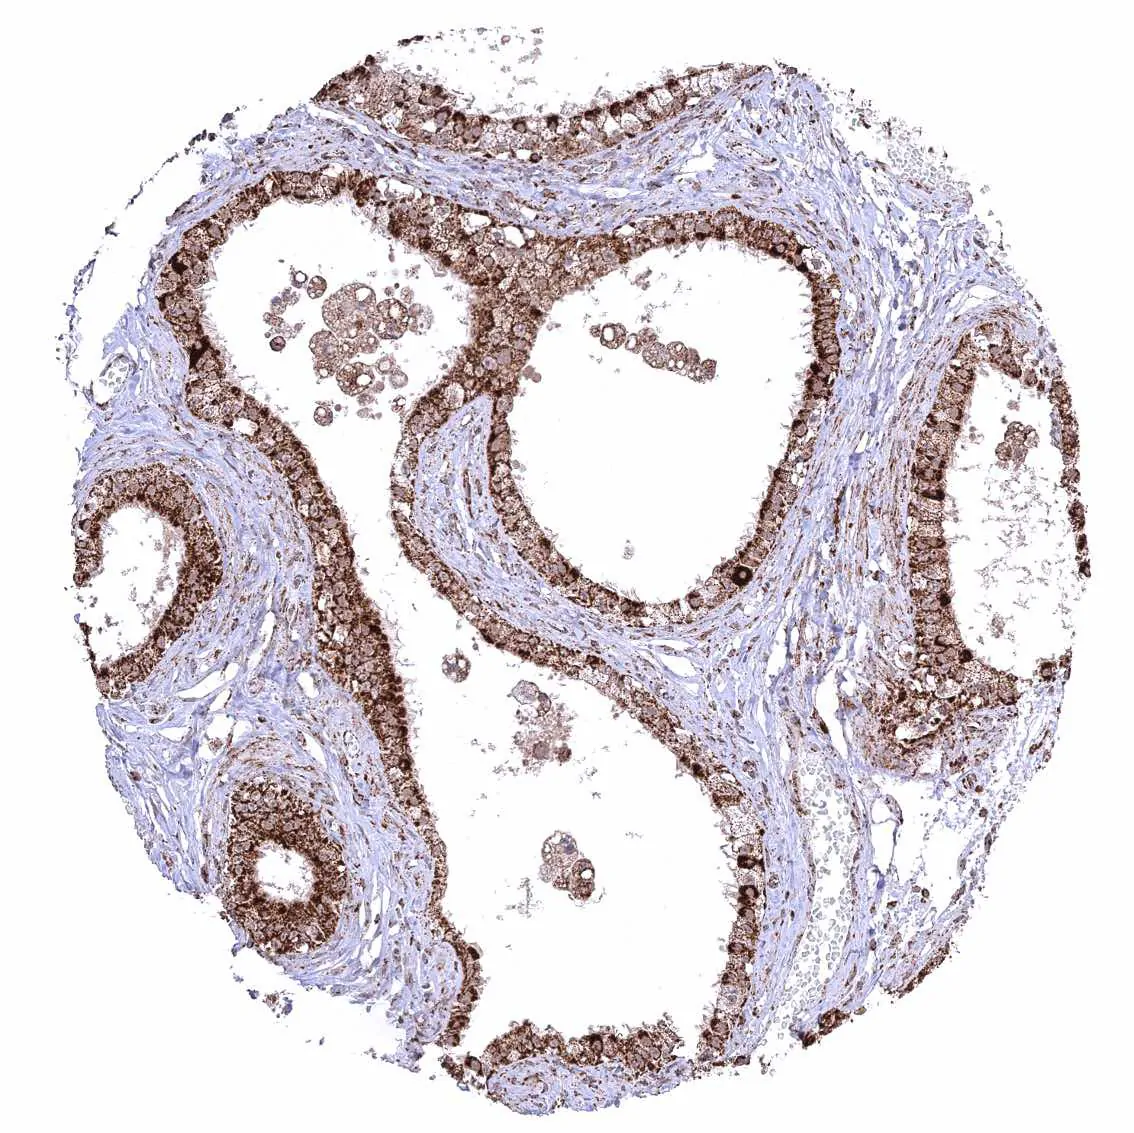

Urinary bladder, muscular wall